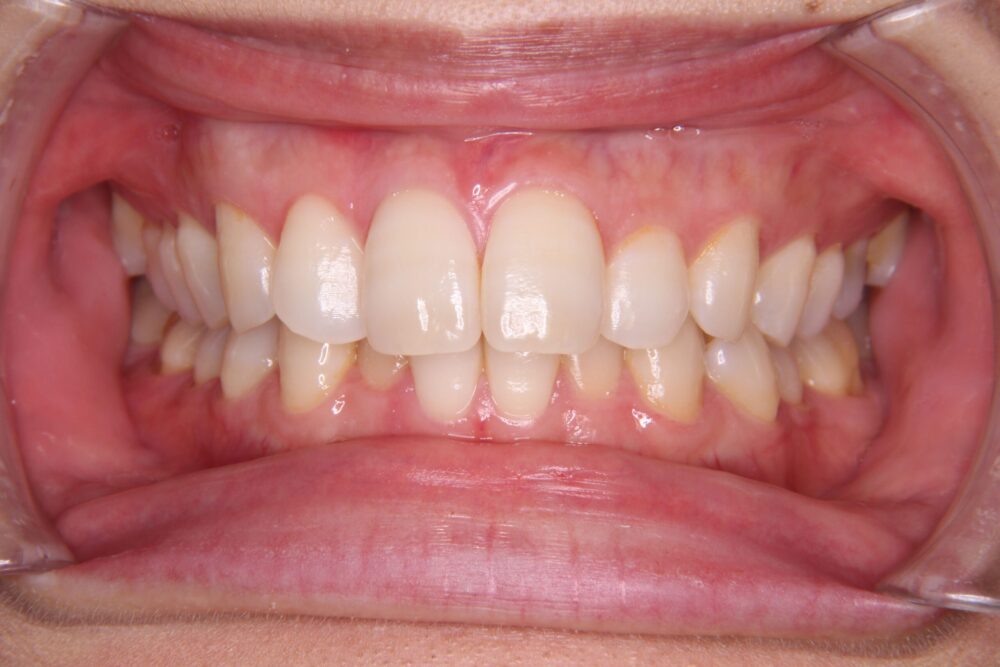

私自身は、特に、「前突」と「下顎の叢生」「過蓋咬合」が気になっていました。

矯正治療前の歯列がこちらです↓↓↓